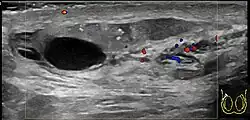

In those who are young and sexually active, gonorrhea and chlamydia are frequently the underlying cause.[1] In older males and men who practice insertive anal sex, enteric bacteria are a common cause.[1] Diagnosis is typically based on symptoms.[1] Conditions that may result in similar symptoms include testicular torsion, inguinal hernia, and testicular cancer.[1] Ultrasound can be useful if the diagnosis is unclear.[1]

Those aged 15 to 35 are most commonly affected.[2] The acute form usually develops over several days, with pain and swelling frequently in only one testis, which will hang low in the scrotum.[3] There will often be a recent history of dysuria or urethral discharge.[3] Fever is also a common symptom. In the chronic version, the patient may have painful point tenderness but may or may not have an irregular epididymis upon palpation, though palpation may reveal an indurated epididymis. A scrotal ultrasound may reveal problems with the epididymis, but such an ultrasound may also show nothing unusual. The majority of patients who present with chronic epididymitis have had symptoms for over five years.[4]: p.311

Diagnosis is typically based on symptoms.[1] Conditions that may result in similar symptoms include testicular torsion, inguinal hernia, and testicular cancer.[1] Ultrasound can be useful if the diagnosis is unclear.[1]

Epididymitis usually has a gradual onset. Typical findings are redness, warmth, and swelling of the scrotum, with tenderness behind the testicle, away from the middle (this is the normal position of the epididymis relative to the testicle). The cremasteric reflex (elevation of the testicle in response to stroking the upper inner thigh) remains normal.[1] This is a useful sign to distinguish it from testicular torsion. If there is pain relieved by elevation of the testicle, this is called Prehn's sign, which is, however, non-specific and is not useful for diagnosis.[13] Before the advent of sophisticated medical imaging techniques, surgical exploration was the standard of care. Today, Doppler ultrasound is a common test: it can demonstrate areas of blood flow and can distinguish clearly between epididymitis and torsion. However, as torsion and other sources of testicular pain can often be determined by palpation alone, some studies have suggested that the only real benefit of an ultrasound is to assure the person that they do not have testicular cancer.[14]: p.237 Nuclear testicular blood flow testing is rarely used.